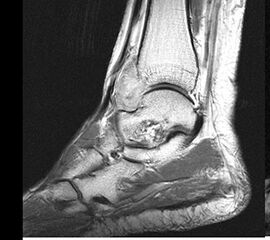

Die Magnetresonanztomographie erlaubt nicht nur die exakte Beurteilung der intramedul­lären und extraossären Tumorausdehnung einschließlich reaktiver Zone, sondern auch die genaue Lagebeziehung zu neurovaskulären Strukturen (Abb. 8) und eine Differenzierung zwischen vitalen versus nekrotischen Tumoranteilen. Dies ist insbesondere für eine mögliche Biopsie von entscheidender Bedeutung um repräsentatives Tumorgewebe für die histo­patho­logische Analyse gewinnen zu können. Die bei Verdacht auf einen Knochen- oder Weichteiltumor vom Radiologen durchzuführenden Standardprotokolle der MRT wurden im Jahr 2006 von der Arbeitsgemeinschaft Muskuloskelettale Diagnostik der Deutschen Röntgengesellschaft veröffentlicht (Tab.2) und gewähren bei entsprechender Umsetzung eine qualitativ hochwertige Untersuchung (DRG, 2006).

MR-tomographische Darstellung eines unspezifischen weichteiligen Raumforderug im Bereich des dorso-lateralen Rückfußes. Die offene Probebiopsie ergab schließlich die Diagnose eines hochmalignen Synovialsarkoms.

Abbildung 34